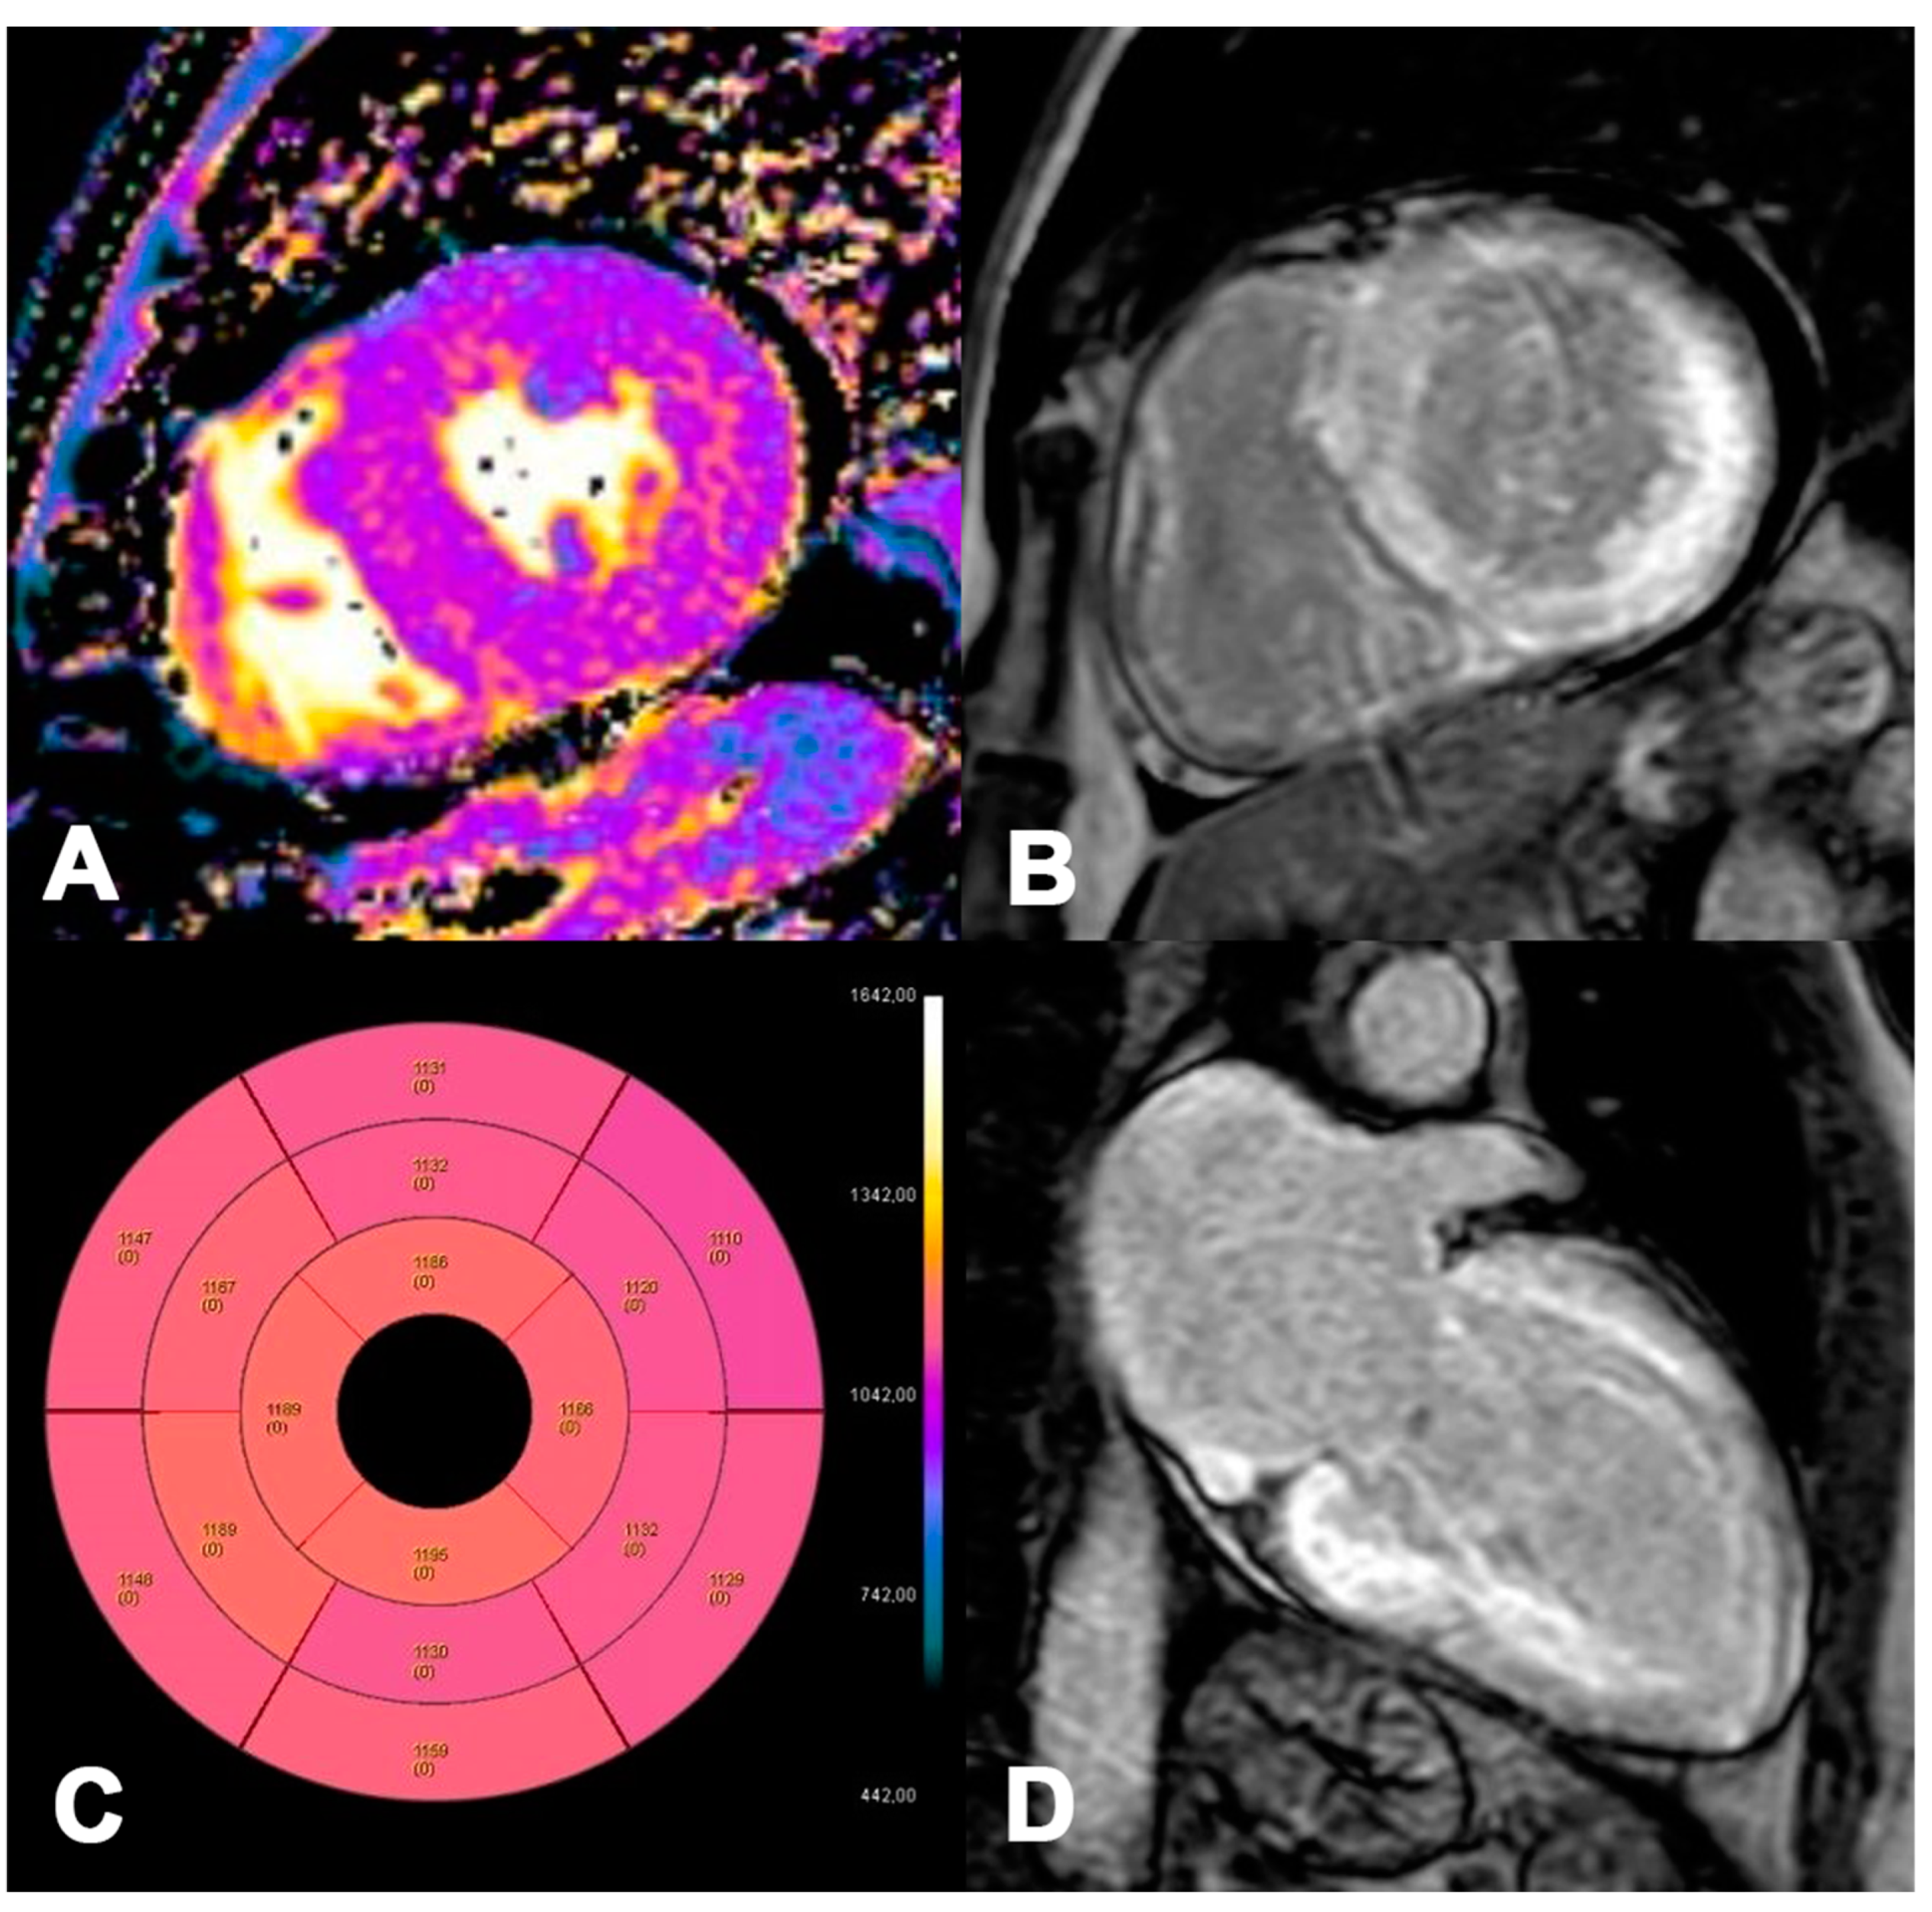

AL 73-year-old patient diagnosed with endomyocardial biopsy. T1 Native Mapping (A) demonstrates a slight increase in value in all entire LV walls with subendocardial patterns. Circumferential subendocardial LGE of the anterior, antero-lateral, and infero-lateral LV wall in two-chamber short (B) and of the SIV to the apical segment in long axes (C). Bullseye map of T1 Native (D). LV, left ventricle; LGE, late gadolinium enhancement.

Figure 7.

ATTR 73-year-old patient diagnosed with endomyocardial biopsy. T1 Native Mapping (A) demonstrates abnormally high values in all entire LV walls in cardiac amyloidosis. Diffuse transmural LV and subendocardial RV LGE in two-chamber short (B) and long axes (C). Bullseye map of T1 Native (D).